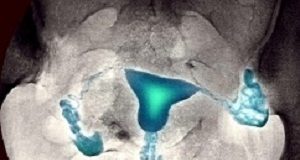

Home Tags Hysterosalpingography (HSG)

Tag: hysterosalpingography (HSG)